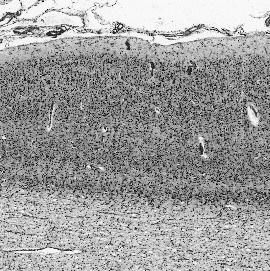

Cytoarchitectonic maps provide microstructural reference parcellations of the brain, describing its organization in terms of the spatial arrangement of neuronal cell bodies as measured from histological tissue sections. Recent work provided the first automatic segmentations of cytoarchitectonic areas in the visual system using Convolutional Neural Networks. We aim to extend this approach to become applicable to a wider range of brain areas, envisioning a solution for mapping the complete human brain. Inspired by recent success in image classification, we propose a contrastive learning objective for encoding microscopic image patches into robust microstructural features, which are efficient for cytoarchitectonic area classification. We show that a model pre-trained using this learning task outperforms a model trained from scratch, as well as a model pre-trained on a recently proposed auxiliary task. We perform cluster analysis in the feature space to show that the learned representations form anatomically meaningful groups.